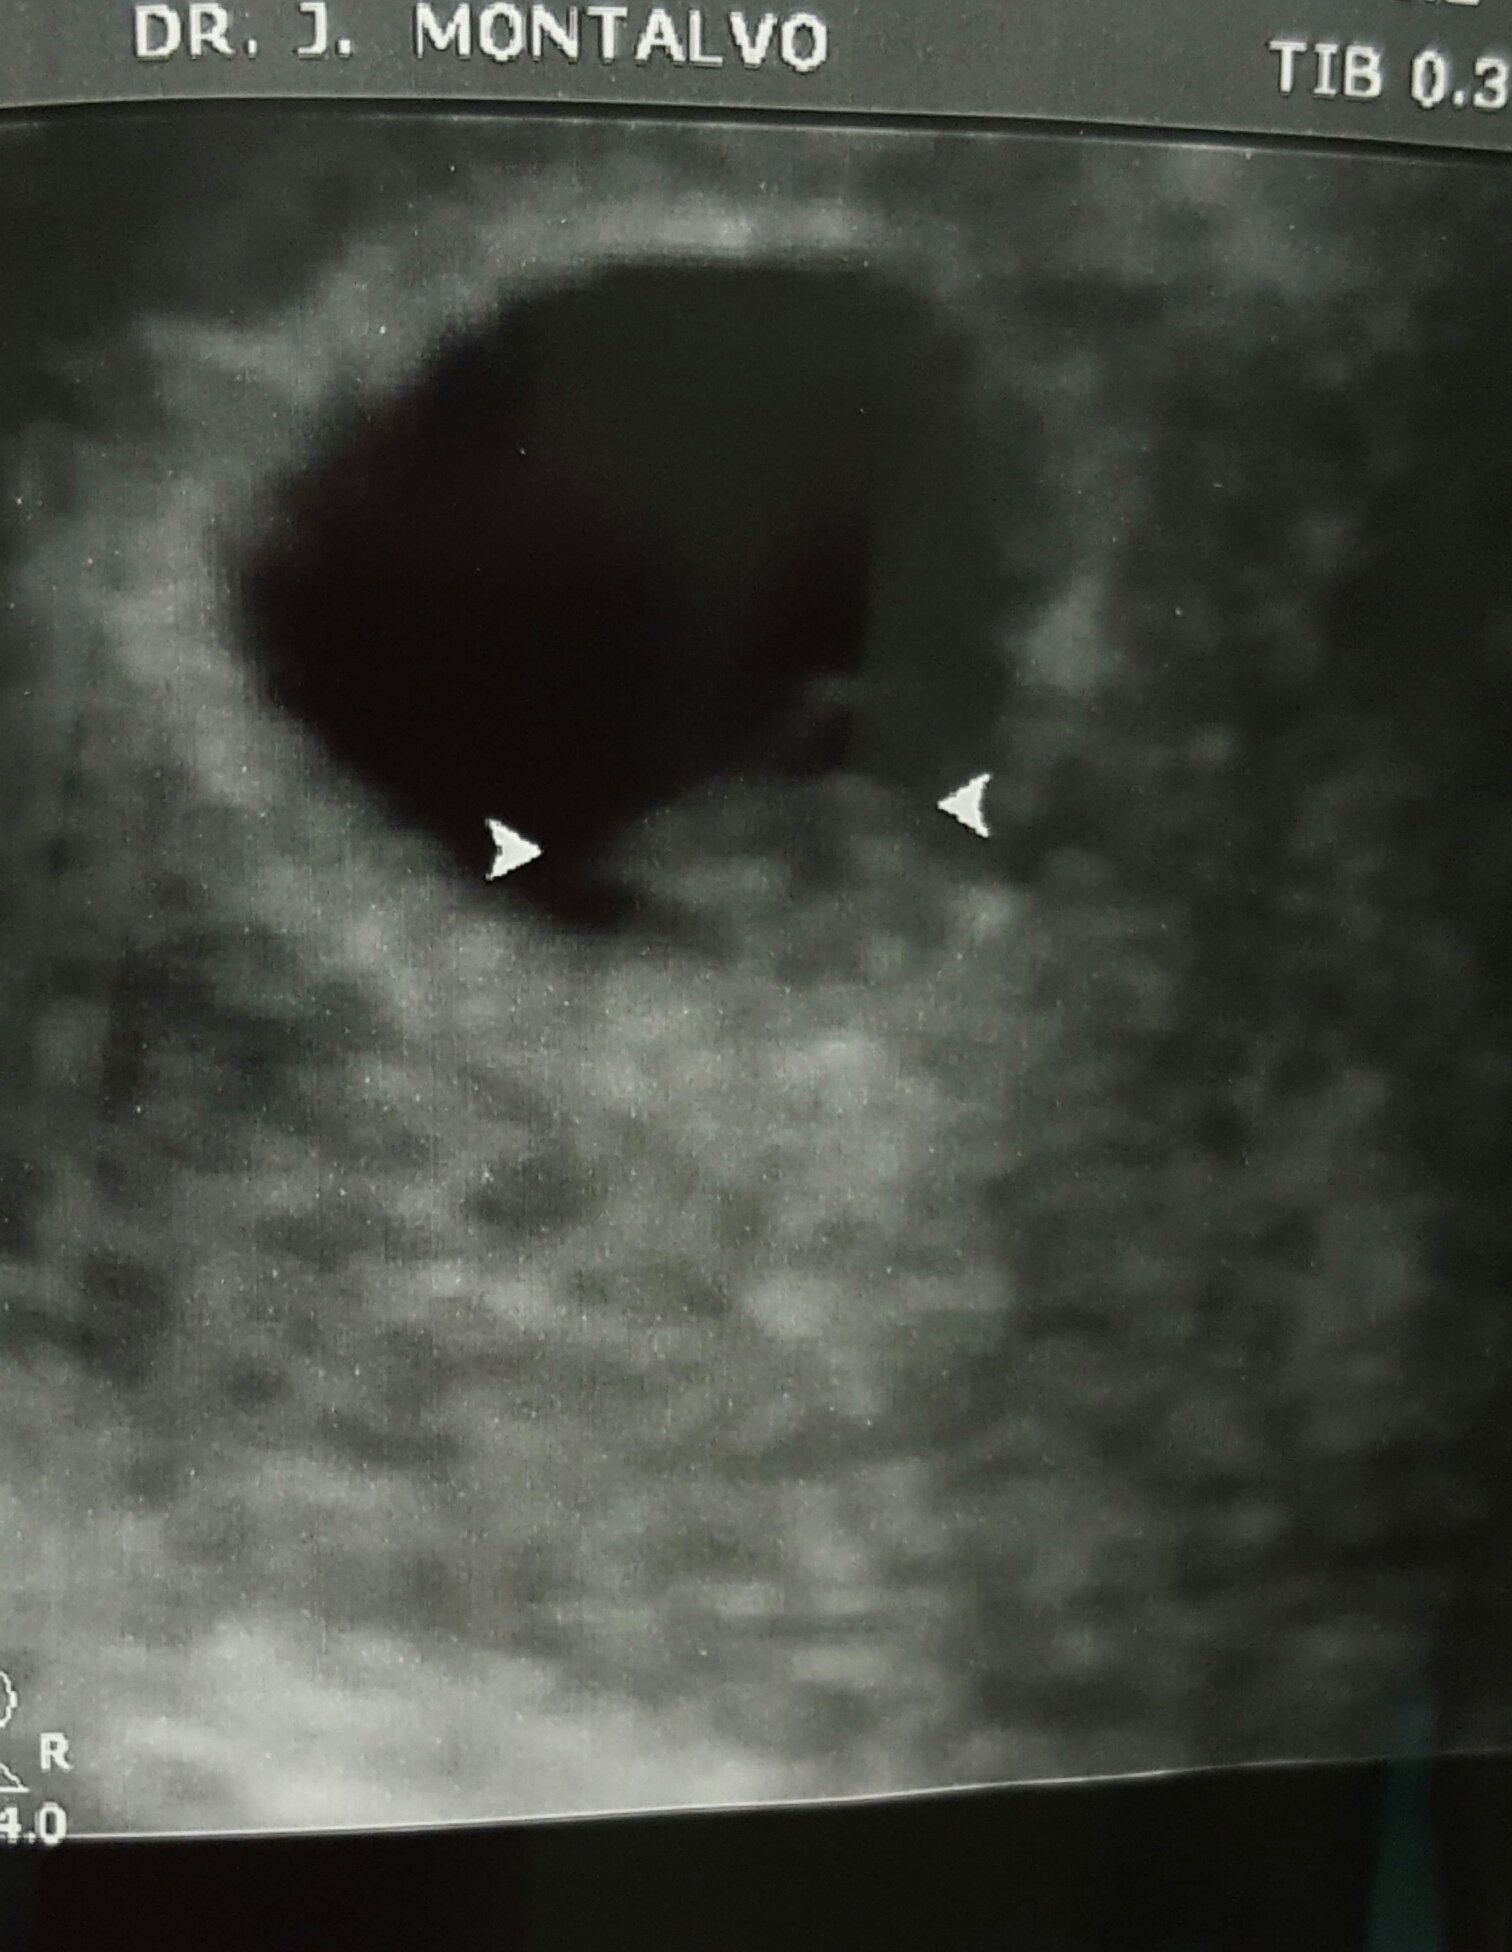

update: since I get to go to the doctor every 1-2 weeks, this is from last Friday.

this is from the high risk obgyn with the better ultrasound machine. good news. she thinks they are monodi but will confirm again in a few weeks

although she is measuring them to be smaller than LMP. by 5-7 days.. due date still in march, ill ask my regular obgyn what she thinks this Friday .

2 little nuggets. good heart rates

147 and 153